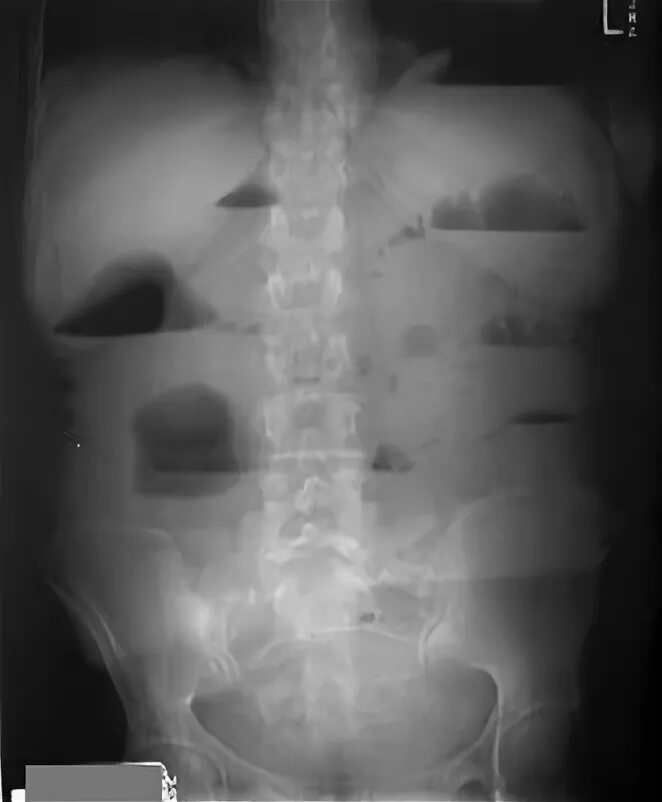

Симптом чаши